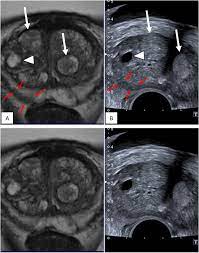

Multiparametric Magnetic Resonance Imaging For The Detection Of Clinically Significant Prostate Cancer What Urologists Need To Know Part 3 Targeted Biopsy European Urology

Multiparametric Magnetic Resonance Imaging For The Detection Of Clinically Significant Prostate Cancer What Urologists Need To Know Part 3 Targeted Biopsy European Urology from els-jbs-prod-cdn.jbs.elsevierhealth.com